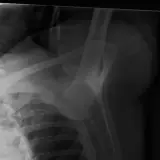

Casos totalmente interactivos con las herramientas que esperaría de un PACS: scroll, ventana, zoom, pan, mediciones, ROI y modo de pantalla completa.

Desplace, arrastre, ajuste ventana y amplíe como en una estación PACS de trabajo